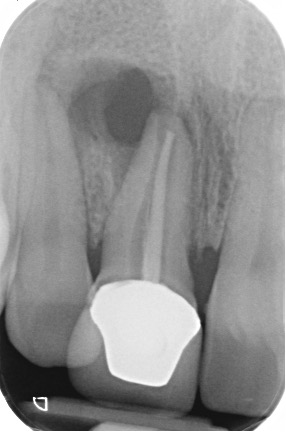

Secondary root canal treatment

Injury to the tooth can cause the root canal to shrink. High magnification and fine ultrasonic instruments are used to locate the root canal.

Fractured teeth

In this case a repeat root filling was completed. This is to minimise risk of infection from the exposed existing root filling. A fibre post and core was placed to build up the tooth sufficiently to retain a crown. This was then restored with an all ceramic crown. If there is insufficient tooth structure sometimes surgery can be carried out. In other cases it may not be possible to restore the tooth.